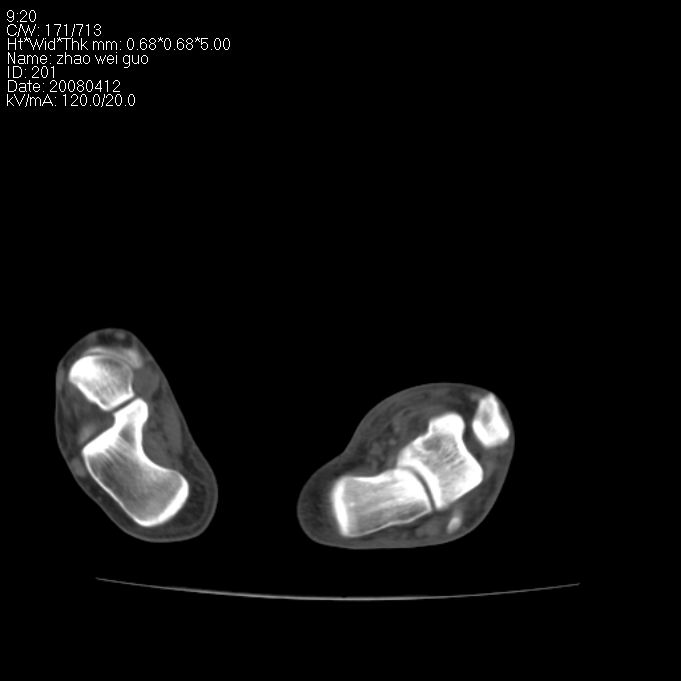

标题: CT12802:男 29岁 踝关节外伤 [打印本页]

标题: CT12802:男 29岁 踝关节外伤

看起来有点乱,不如平片好看,柘跖骨粉碎性骨折。

左侧跖附骨多发骨折

(左?)侧跖附骨多发性骨折。

左侧跖跗骨多发骨折.请结合平片进一步定位。

左侧跖附骨多发骨折。

左侧跗跖骨多发骨折

左侧跖附骨多发骨折,平片完全可以解决;没有必要。